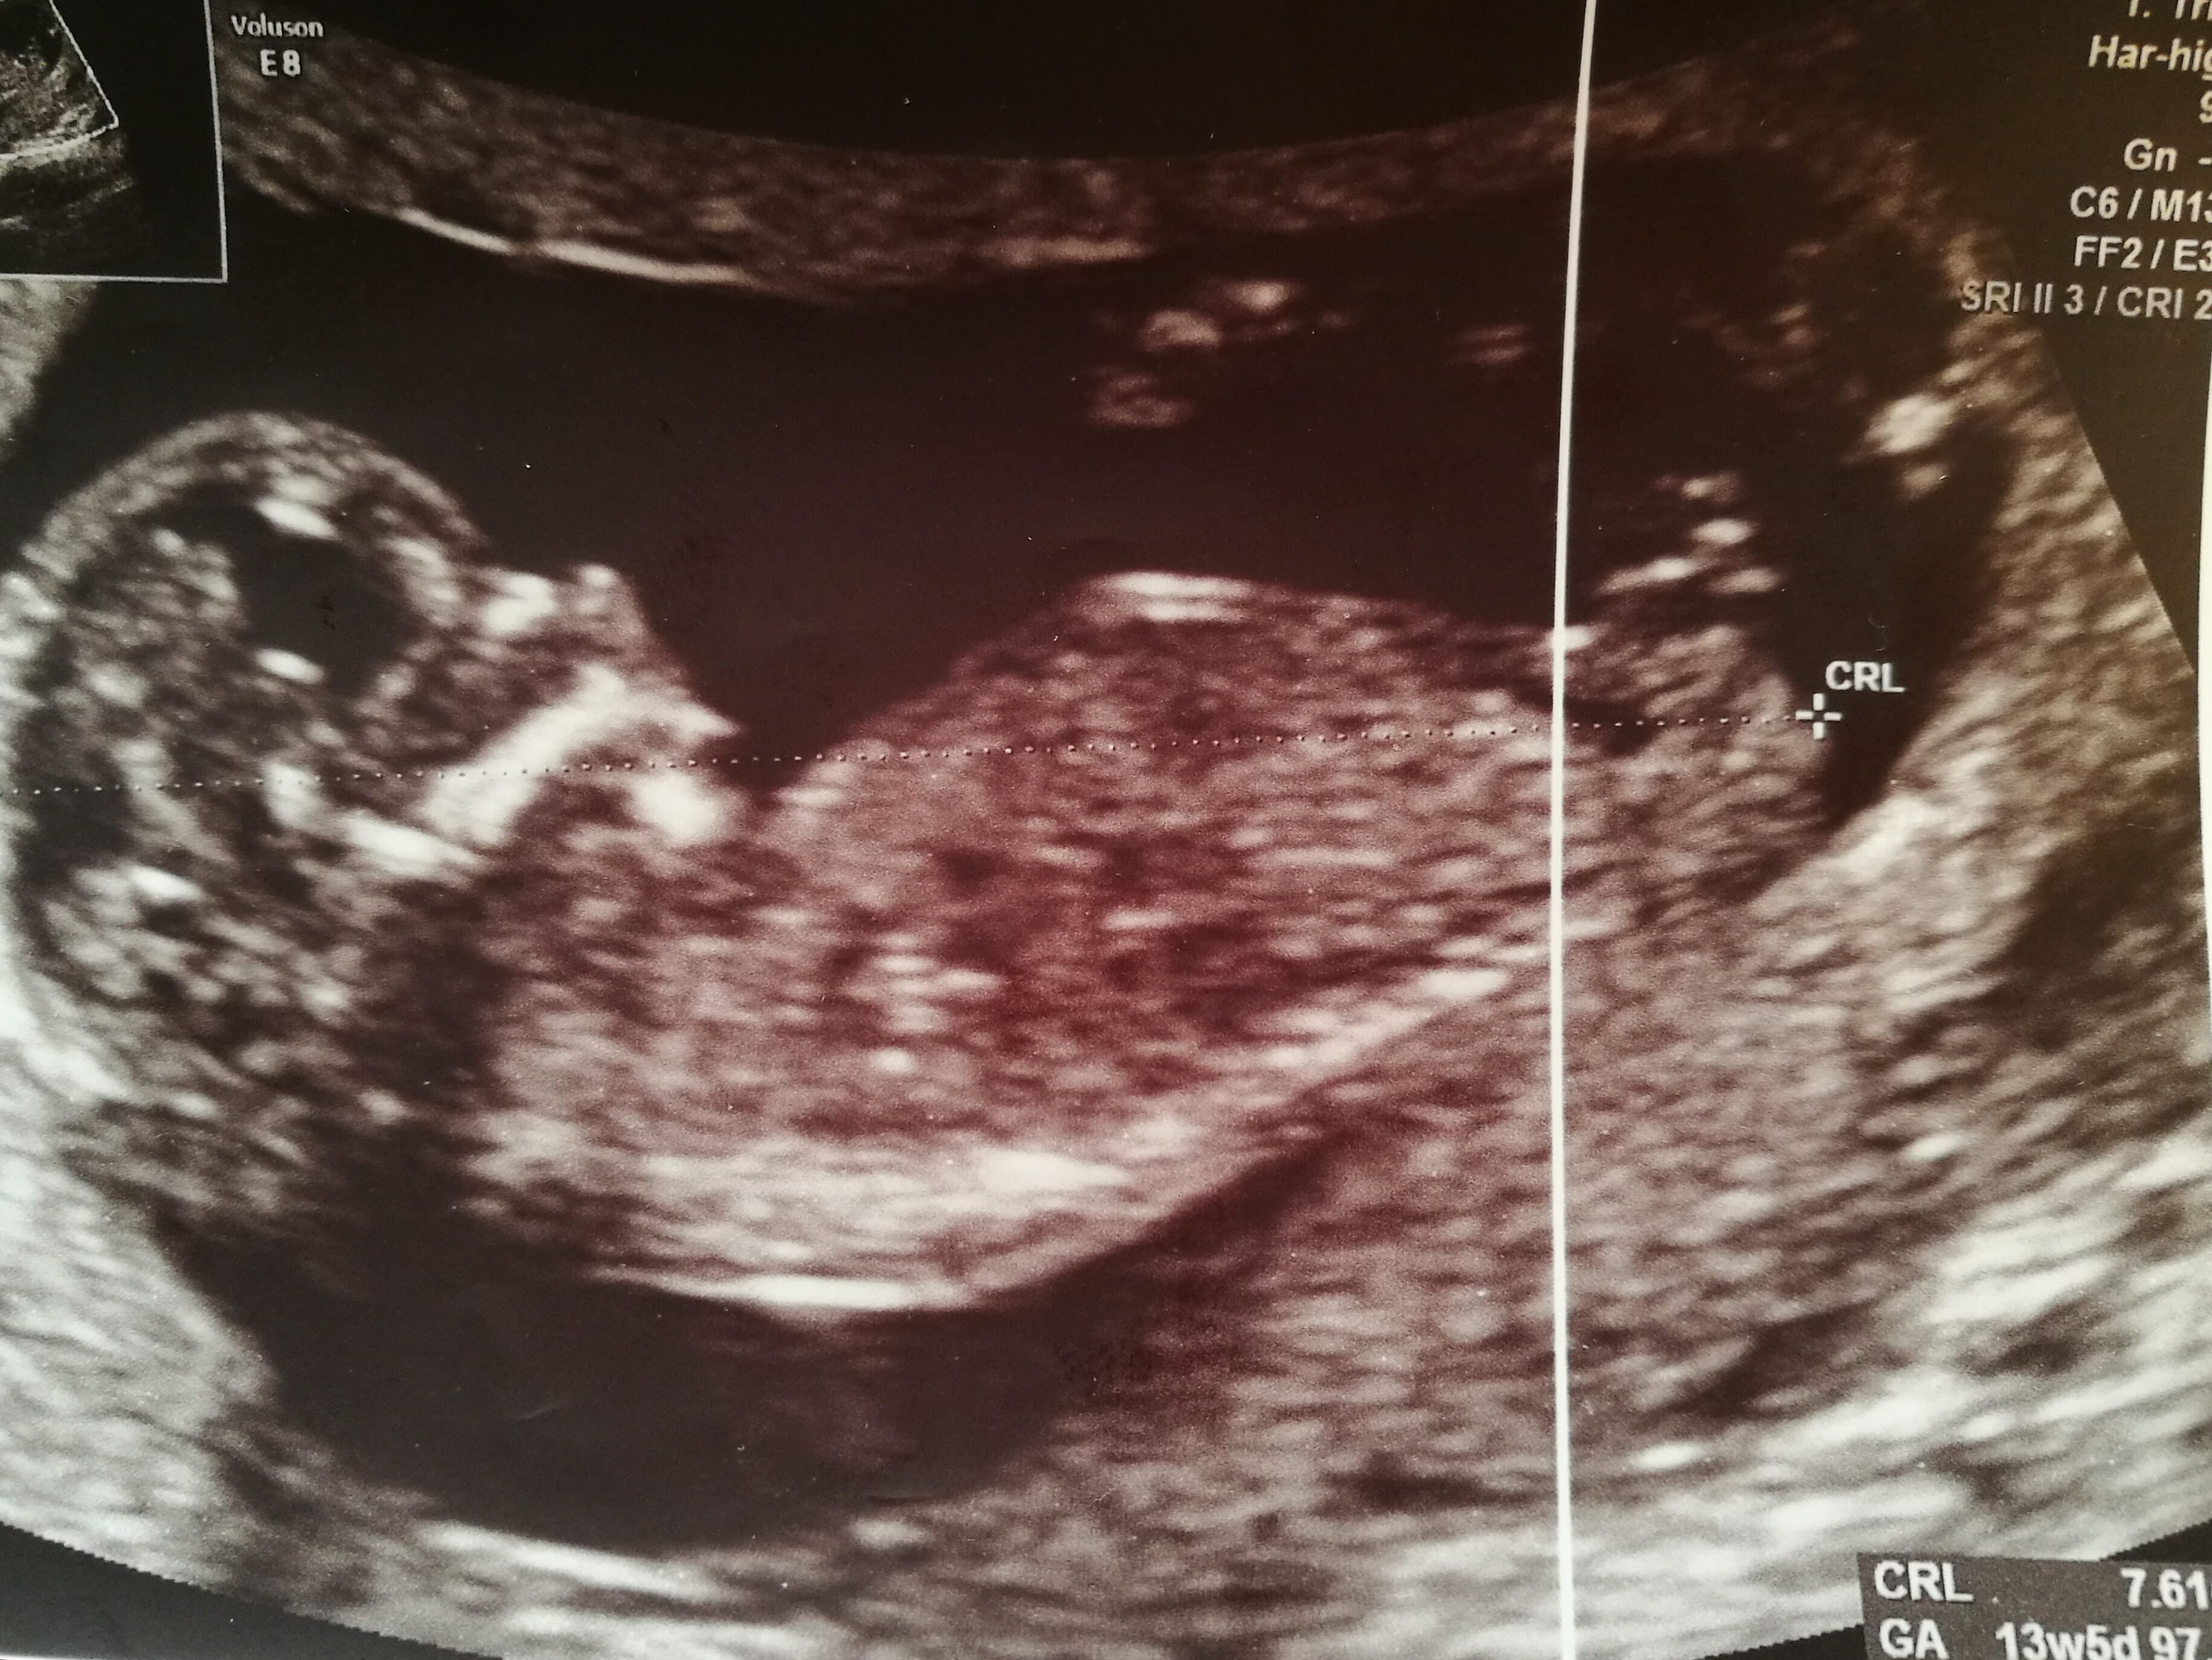

Little Girls :)

Attachment 10886

Above is a link to a perfect picture of what to look for for a girl. The nice long flat white line, and if your lucky you may see it as two flat white lines with a second small line running parallel to the main flat white line often referred to as part of a fork, I see it as the edge of the lips showing below the inner nub. If on a picture the seperate small white line is showing above the main white line then there is always a chance that it could be the smallest part of a boy nub just out of focus, so keep your eyes peeled on your scan!

So you can see above how on an ultrasound a girls bright white nub line is flat and how it can often appear as longer as her inner part is pointing out of the bottom of baby and how it can look like two lines.